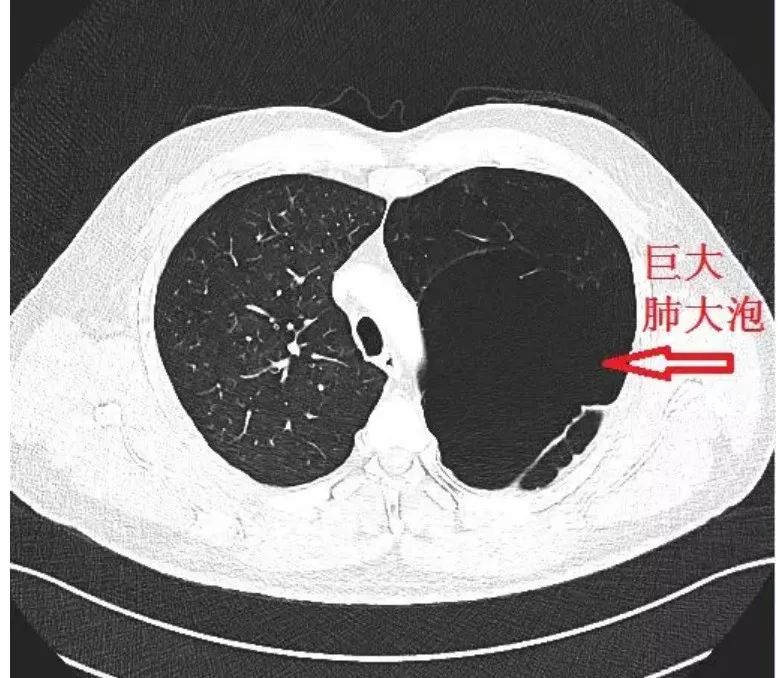

肺大泡CT,肺气肿CT

术前胸部ct提示两肺多处巨大疱病变

因胸闷2月余于外院行胸部ct:右肺发现巨型肺大泡

值得深思的「肺大泡」,这个陷阱千万别踩